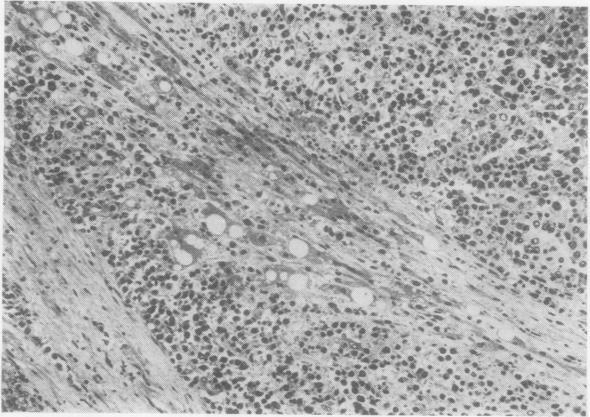

The clinical and pathological findings of a case of systemic angioendotheliomatosis are presented. The previously published cases of this disease are analysed. The present case is only the third to show clear evidence of metastasis.

本文报告了一例系统性血管内皮瘤病的临床及病理表现。对该疾病既往已发表的病例进行了分析。本病例是第三例有明确转移证据的病例。